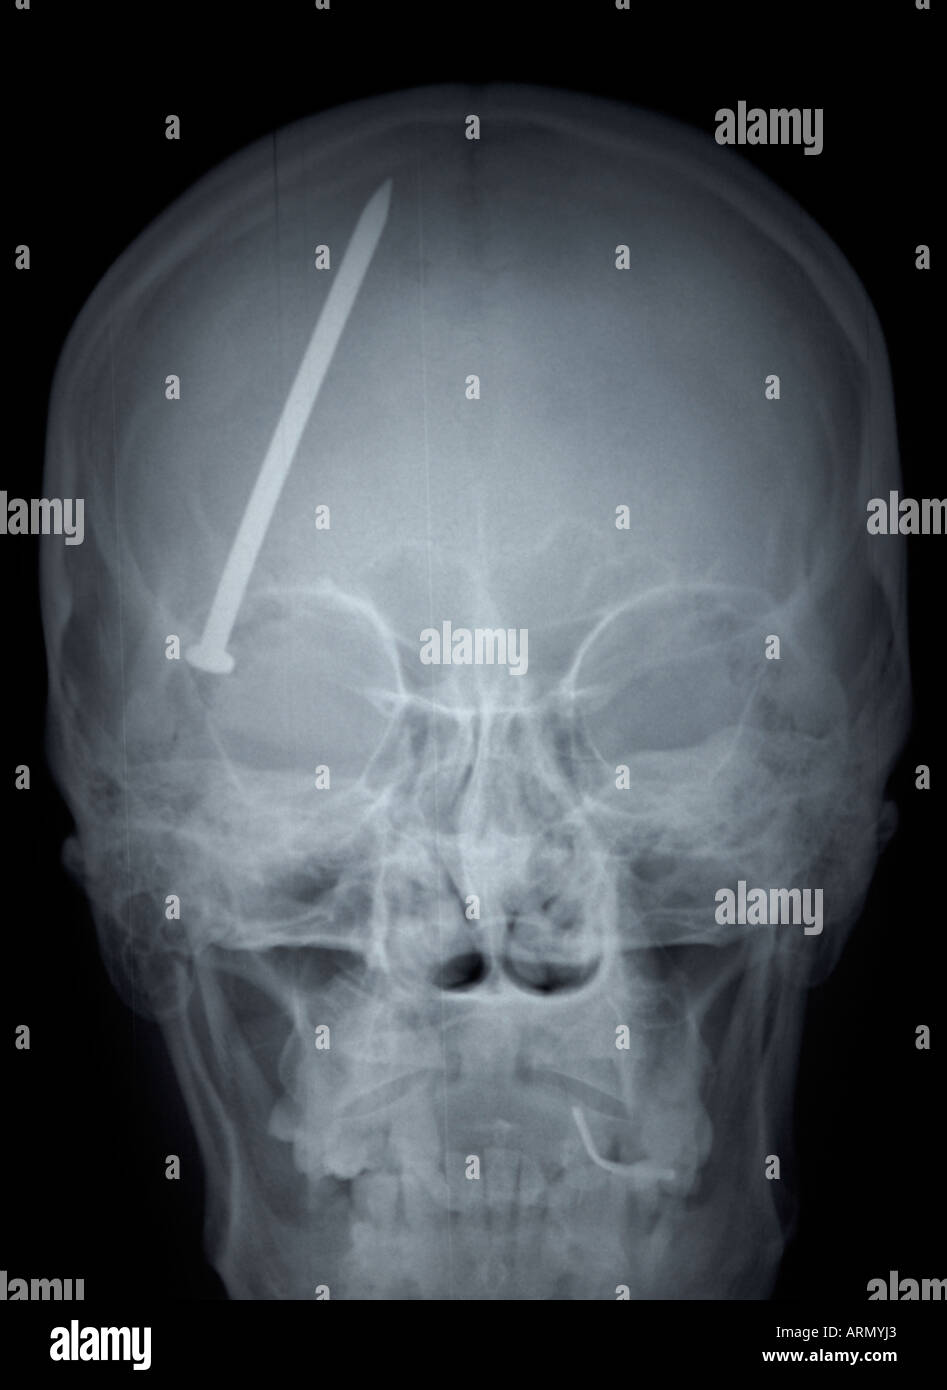

frontal xray of adult skull with nail in head Stock Photo Alamy Drill Bit In Head X Ray   note the everted loop of the transnasal wire (black star), the exposed drill bit (black arrow head), the orbicularis muscle (o), the. Patients typically present with a combination of reduced glasgow coma scale (gcs),. 1 a) and a computed tomography (ct) scan of the head (fig. 1 b) demonstrated a hyperdense. The tip of the object.    — cranial. Drill Bit In Head X Ray.